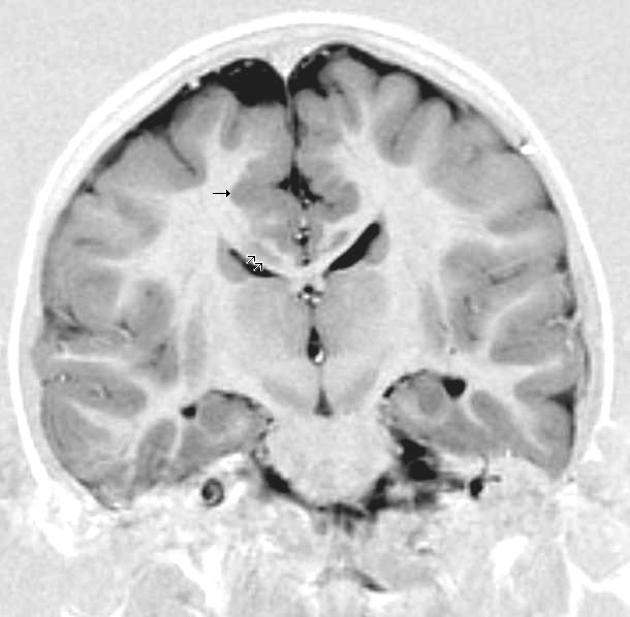

The researchers gathered a PHIV-positive cohort from the NIH Pediatric HIV/Aids Cohort Study network, and a control group from the Pediatric Imaging, Neurocognition and Genetics study. Both groups were frequency-matched for sex and age. To determine PHIV severity, each individual was tested for CD$ T-lymphocye oercentages (CD4%) and plasma HIV RNA concentrations. The former was used to determine disease severity, and the latter to determine viral load. They also recorded the lowest known lifetime CD4% and highest known lifetime RNA concentrationCortical and subcortical grey matter volumes were measured for certain regions of interest (ROIs) using structural MRIs.

The results indicated that PHIV infected youth had significantly smaller volumes in the ten primary ROIs. Peak VL load also negatively correlated with total grey matter, suggesting that increased PHIV severity corresponded to lower volumes. Higher VL also correlated with reduced grey matter in the bilateral rostral middle and superior frontal lobes. These results were sustained even after adjustment for sex, age, caregiver educational attainment, race, annual household income and intracranial volume.